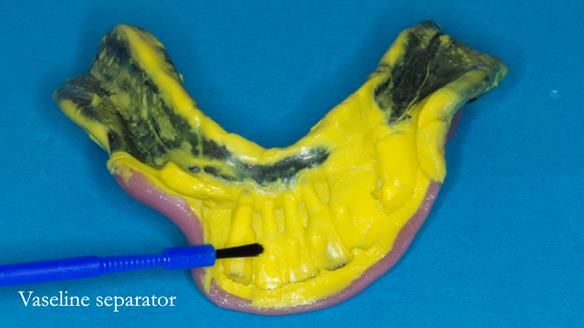

- a good approach to relining distal extension RPDs, similar in principle to the altered cast technique

An honest note on the impressions

It’s important to say that I struggled considerably to obtain accurate impressions of Ken’s lower anterior teeth. This was a difficult situation and not one that went smoothly.

At one stage, a tray became locked in position and had to be sectioned and removed carefully. This is not something I like but it does happen, particularly in cases with long, thin teeth and compromised anatomy.